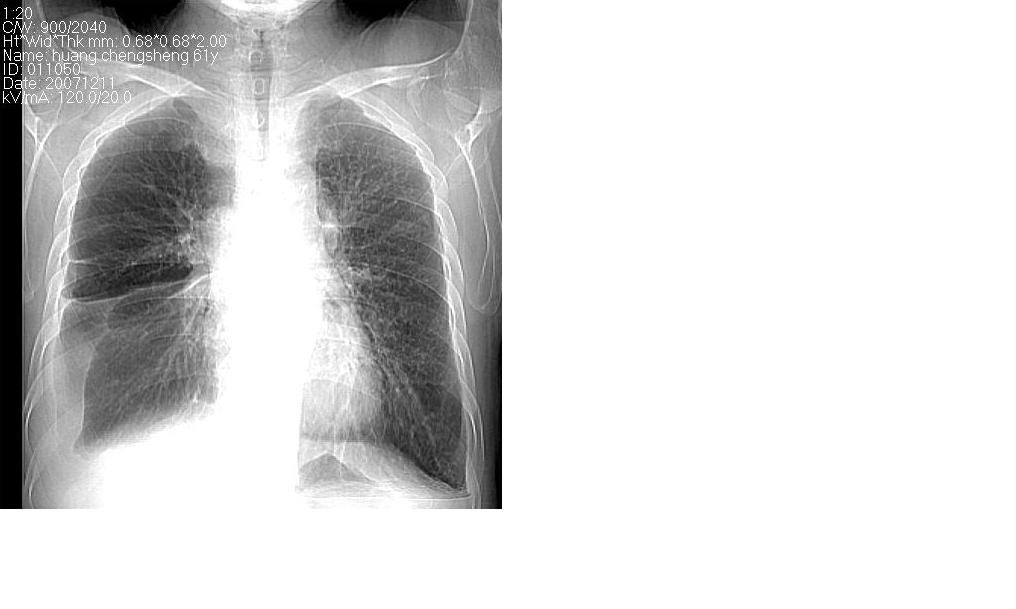

标题: CT10843:男 61岁,胸部CT平扫 [打印本页]

标题: CT10843:男 61岁,胸部CT平扫

男 61岁,已确诊肺癌半年余.

右肺小细胞肺癌并纵隔淋巴结转移。胸腔积液,心包少量积液。左肺改变不除外癌性淋巴管炎

考虑:1、右肺下叶中心型肺癌并纵隔淋巴结转移。胸腔积液。

2、心包少量积液。

3、左肺改变不除外癌性淋巴管炎或化疗后肺间质纤维化。